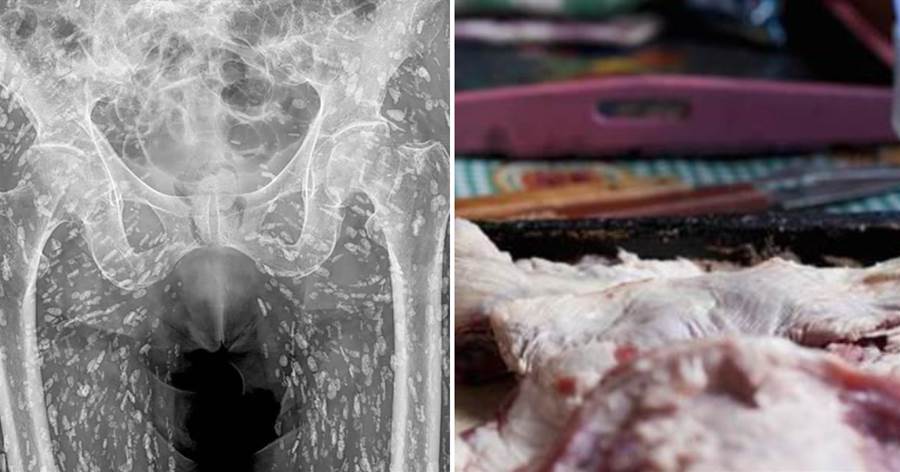

X光檢查主要用于觀察骨骼和關節,有時也會用于檢測軟組織 (如器官),作為醫師診斷多種疾病損傷的依據,被說是人體健康的照妖鏡也不為過。泰國一名婦人做X光檢查,結果影像顯示她體內佈滿密密麻麻的白點,沒想到這背後竟藏了超噁真相。

根據媒體《Khaosod》的報導,一名泰國網友「Ai Jaeo Mueang Chan」在臉書分享,自己過去在擔任X光助理時,一名婦人到診所拍攝從髖部到腿部的X光,結果影像一出來佈滿詭異陰影,放射科醫師一看,指出這些白點其實全是寄生蟲!他直言,當時的畫面就像下圖:

醫師推測這患者疑似是長期吃生食、生肉,這才間接將寄生蟲的蟲卵或幼蟲吃下肚。在場醫護人員聽了全都嚇傻,看著全身都是寄生蟲的X光,有人狂起雞皮疙瘩,有人則是不斷用酒精洗手。

事件曝光後,有專家就因此提醒,吃生食有感染絛蟲病的風險,若體內有寄生蟲,恐會出現不斷飢餓、上腹疼痛、腸胃不適、消化不良、噁心嘔吐,腹瀉、便祕、體重減輕等癥狀,避免感染寄生蟲的方法,就是食用肉類要充分煮熟,處理肉類時也要注意衛生、確保生熟食分離,避免交叉感染。